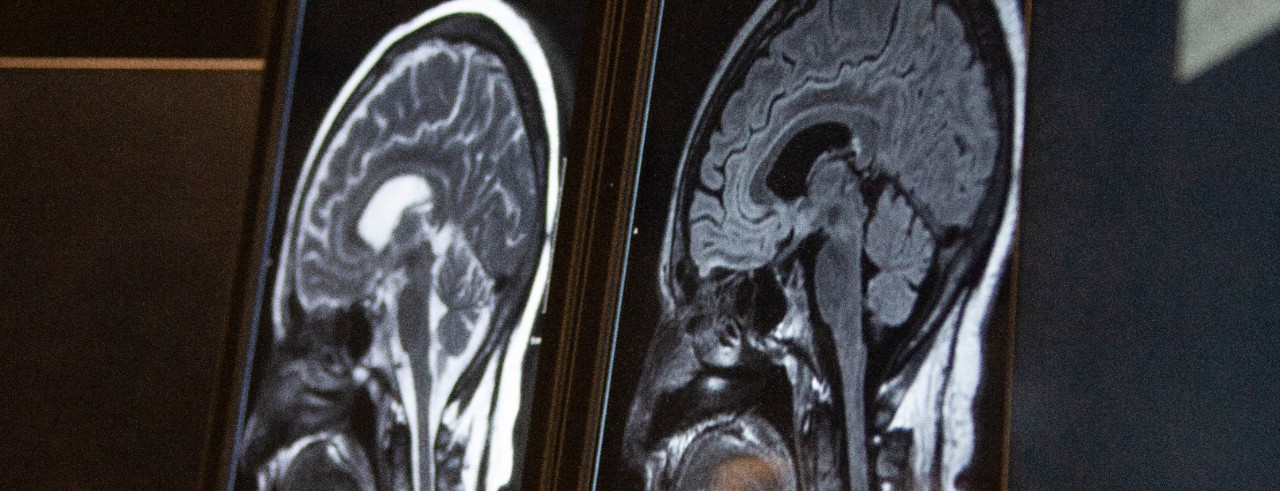

Hyacinth said that the cerebral small blood vessels can develop disease that can result in “tiny strokes,” the deterioration of healthy neuron fibers (called white matter hyperintensity) and small amounts of bleeding in the brain (called cerebral microbleeds), but the symptoms usually are not severe enough in the acute stage to be identified clinically. Typically, cerebral small vessel diseases (CSVD) are identified through MRI scans.

The UC study will research whether there is a higher disease burden of CSVD in non-Hispanic Black patients compared to non-Hispanic white patients by analyzing MRI scans from participants who developed stroke or TIA while enrolled in a parent study known as REGARDS. Hyacinth said this dataset of stroke patients is being used because otherwise healthy people do not typically have MRI scans to analyze.

Featured photo at top of MRI brain scan. Photo/Ravenna Rutledge/University of Cincinnati.